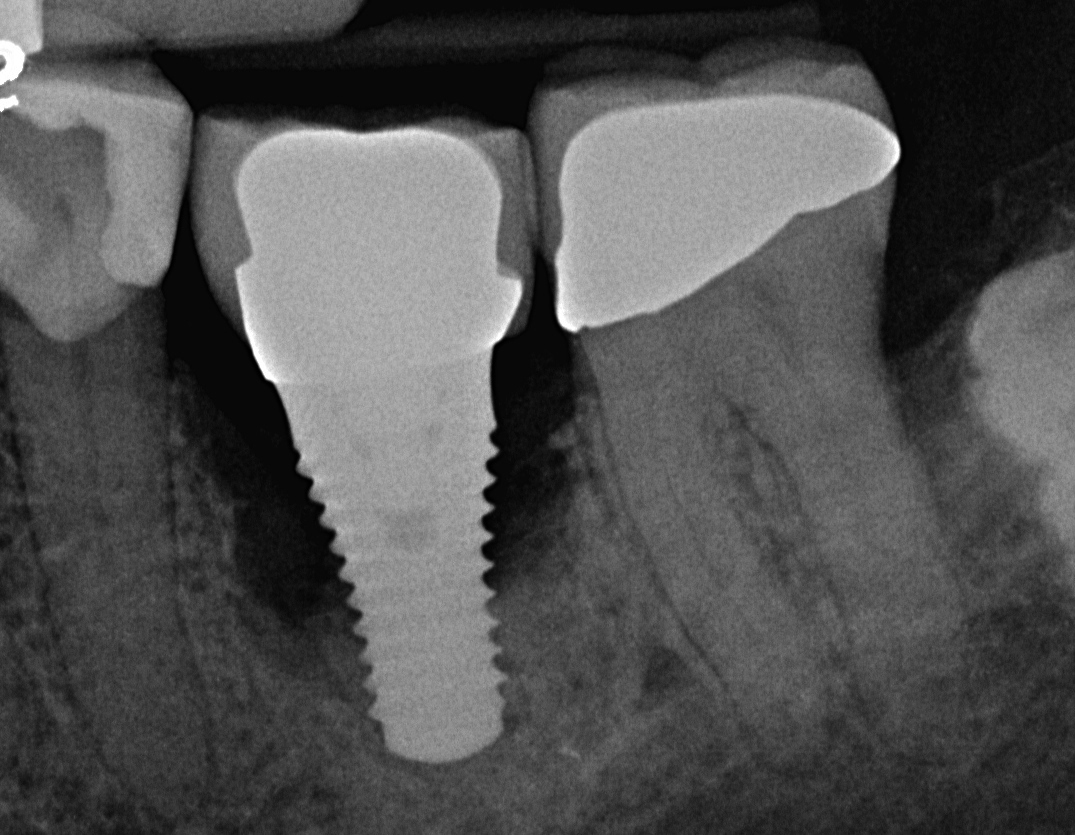

Fig 11. Radiograph taken 1 year after regenerative therapy suggests favorable bone gain covering the entire roughened surface of the dental implant.

Figure 11